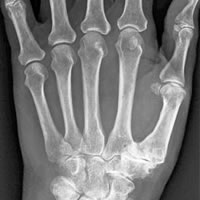

The joint at the base of the thumb (Carpometacarpal or CMC joint) is made up of 2 bones, the thumb metacarpal and the trapezium. It is a saddle shaped joint and very mobile, allowing movement of the thumb in many directions. Because it is so mobile and is used a huge amount it is prone to" wear and tear" or osteoarthritis, destroying the smooth cartilage of the joints; this results in painful bare bone grinding on bare bone.

YES. All patients require x-rays of the thumb base and surrounding joints to assess the degree of arthritic change and allow for pre-operative planning.